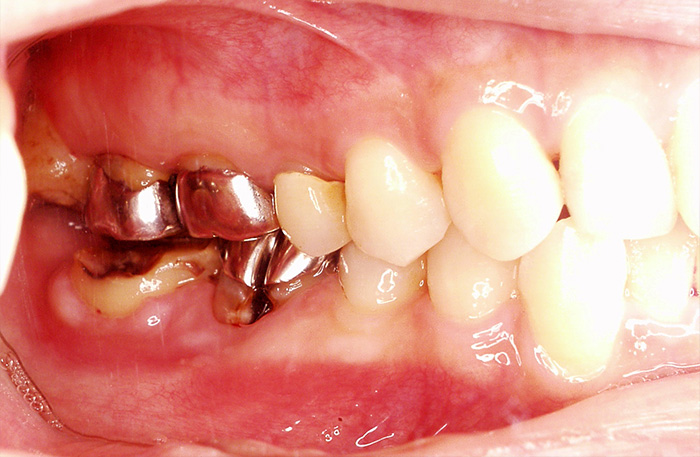

歯の移植の症例

Before

親知らずの歯を移植したケースです。患者様はとても喜ばれておりました。